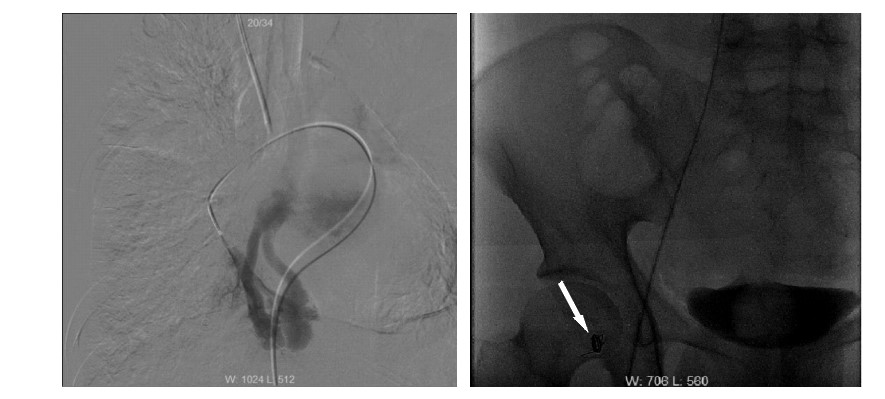

患者男性,25岁,因“突发抽搐后摔倒3 h余”于2014年2月23日诊断“外伤性硬膜下血肿”入我院神经外科,否认既往重大疾病史。急诊头颅计算机断层扫描(computed tomography,CT)及核磁共振成像(magnetic resonance imaging,MRI)均提示“左侧额颞部少量硬膜下血肿”。入院时患者浅昏迷,躁动不安,格拉斯哥昏迷评分(glasgow coma scale,GCS)11分,双侧瞳孔等大,光反射灵敏,两肺听诊未闻及明显干湿啰音,心律齐,无明显杂音,四肢均有活动,杵状指。入院后患者氧饱和度偏低,不吸氧时指脉氧饱和度波动在85%~90%之间,血常规:白细胞计数 10.4×109 L-1、中性粒比例 76.4%、血红蛋白 153 g/L,肝肾功能均正常范围,考虑患者有杵状指,予预约心脏彩超。入院第二日(2月24日),患者神志转清,有指令动作,对答切题,已可下床活动。2月27日患者在家属搀扶下上厕所时,突发心搏骤停,当时立即予以气管插管以及持续胸外心脏按压等心肺复苏抢救,约110 min左右,患者恢复自主心律并转入ICU进一步抢救及治疗。入ICU时患者双侧瞳孔等大,光反射存在,并随即出现四肢躁动,遂予持续镇痛镇静治疗,并予亚低温脑保护(头部冰帽及盐酸氯丙嗪+异丙嗪静脉维持,维持体温在34 ℃左右),小剂量去甲肾上腺素 维持MAP在90 mmHg(1 mmHg=0.133 kPa)左右,机械通气支持等治疗,患者氧合、循环基本稳定,亚低温治疗48 h左右(3月1日)予复温,患者有自主睁眼,四肢均有活动,期间予床边心脏超声检查(采用右侧锁骨下静脉注射5%碳酸氢钠溶液+维生素C微泡造影)发现左室微泡显影,考虑肺动静脉瘘可能(图 1),予预约胸部增强CT检查,3月3日中午,患者突发大咯血,咯血量达近800 mL,予提高呼吸机支持条件等抢救处理后患者咯血停止,氧饱和度维持在90%以上,予急诊肺动脉增强CT扫描发现患者多发肺动静脉瘘,分别位于左上肺、右上肺及右下肺(图 2),随即组织本院胸外科、介入治疗科以及心内科等相关科室讨论后考虑患者肺动静脉多发,手术治疗需切除肺叶面积极大,故首选介入栓塞治疗,经家属签字同意后,当天即予急诊数字减影血管造影(digital subtraction angiography,DSA),术中见患者左上、右下肺动静脉瘘均为双支动静脉瘘畸形,右上造影未见畸形血管,考虑血栓形成可能;尝试左上及右下肺动静脉瘘弹簧圈栓塞治疗,最终左上肺动静脉瘘栓塞成功(图 3),右下肺动静脉瘘管径过大,血流速极快,弹簧圈(本院最大直径)无法固定(图 4),漂移至右髂外动脉,予床边动脉切开取出后结束治疗返回病房。再次告知家属拟行开胸肺动静脉瘘切除手术治疗(右下肺),家属因费用问题拒绝手术治疗,至3月5日,患者再次出现大咯血,抢救无效死亡。

心尖部四腔心,箭头示左心大量微泡显影 图 1 床旁心脏超声微泡造影